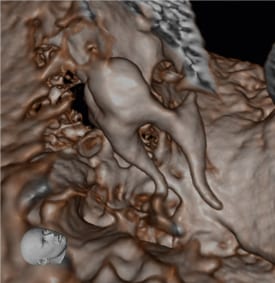

- Phẫu thuật miệng hàm mặt: lên kế hoạch cắt xương, u nang, u xương hàm

- Đánh giá TMJ: hình ảnh lồi cầu 3D, không gian khớp